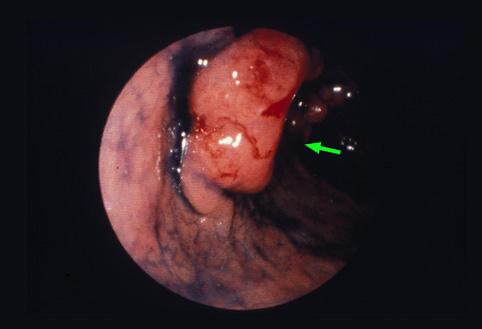

Cáncer Avanzado del Estómago tipo I (Tumoral), crecido en la Pared Anterior

Tumor Epitelial Maligno/Adenocarcinoma

estómago(región)/antro

Endoscopia

Tipo 1(Tipo protuído)/

25 - 29

s(a)